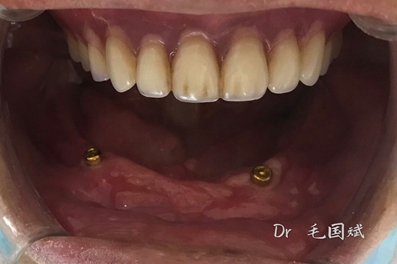

毛國(guó)斌種植病例——群討論分享